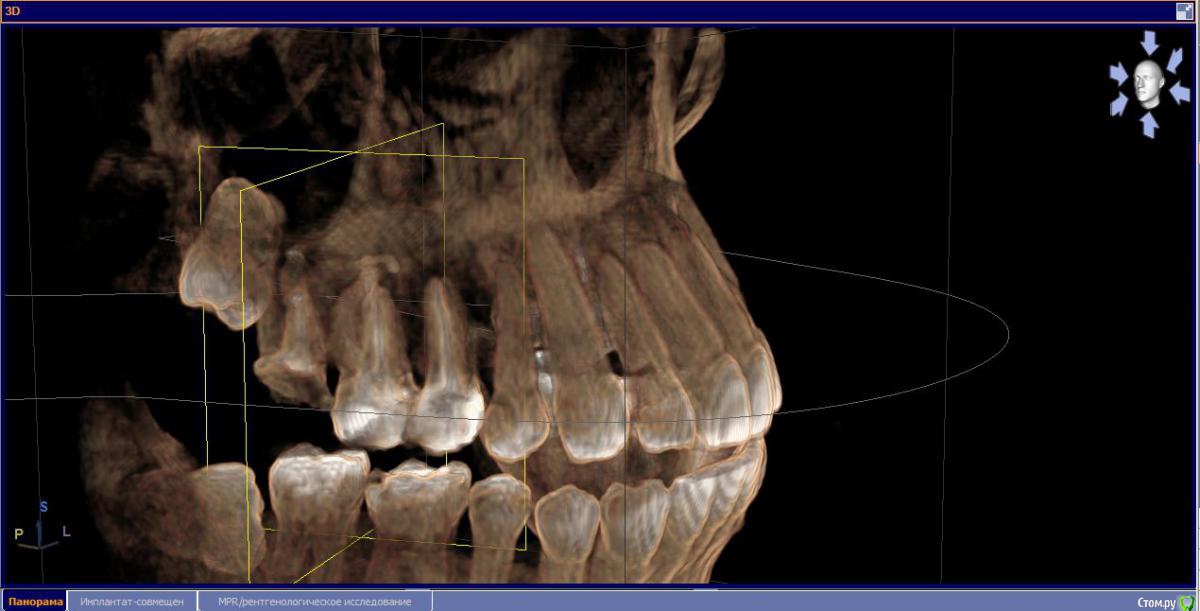

М, 33 года. Есть показания к одновременному удалению 16-го зуба - киста, и 17-го - разрушена верхушка. 8-й предлагают оставить, чтобы "держал кость" (как то так мне озвучили).

Через 3-4 месяца рекомендуют синус-лифтинг и установку двух имплантатов.

- Возможно ли консервативное перелечивание 16 зуба и есть ли смысл?

- Насколько опасная имеется киста?

и 6 и 7й зубы не выглядят 100% кандидатами на удаление.

1.6 большая вероятность сохранить,но понятнее при очном осмотре и диагностическом вскрытии. 1.7,скорее всего,не жилец,но тоже очно взглянуть на него стОит